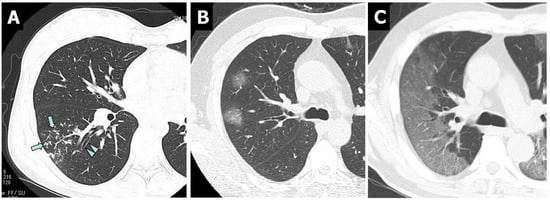

3.4. Chest CT Findings